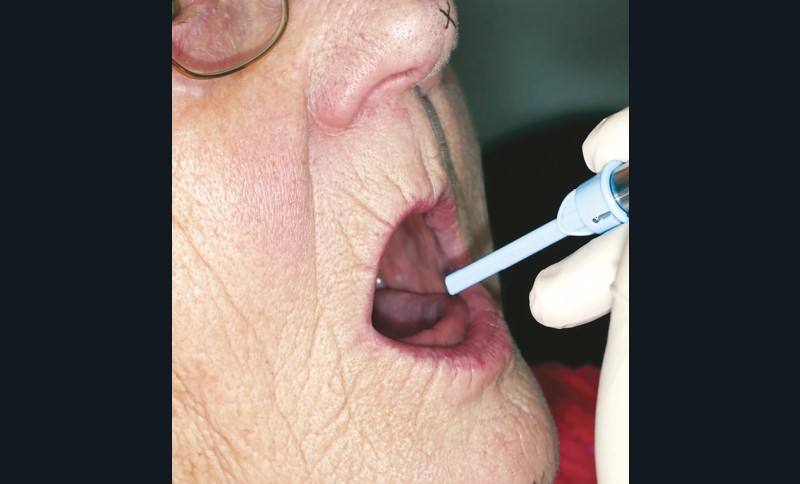

On peut aussi se servir de la déglutition pour valider le choix de la DVO. Si elle est surestimée, le patient aura tendance à se pencher en avant pour déglutir ; en cas de sous-évaluation le patient aura tendance à interposer sa langue entre les deux arcades préfigurées (fig. 22) [8].